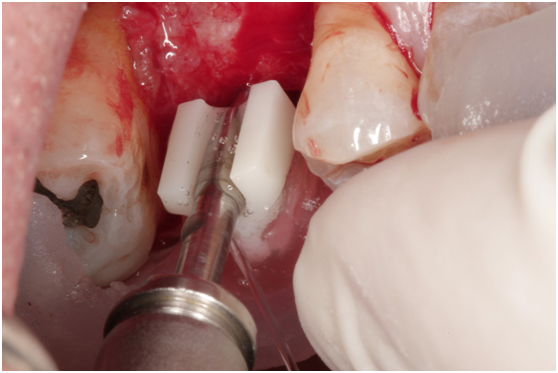

患者之後於96/11/08在右下第一小臼齒與植體間有膿胞產生,並於97/02/21確認右下第一小臼齒有根裂的情形,因此在97/02/29拔除此牙;經過將近半年後,於97/09/23放置一顆植體於此位置

97/09/18 拔牙半年後安排右下第一小臼齒植牙前

97/09/23 右下第一小臼齒植牙完成時